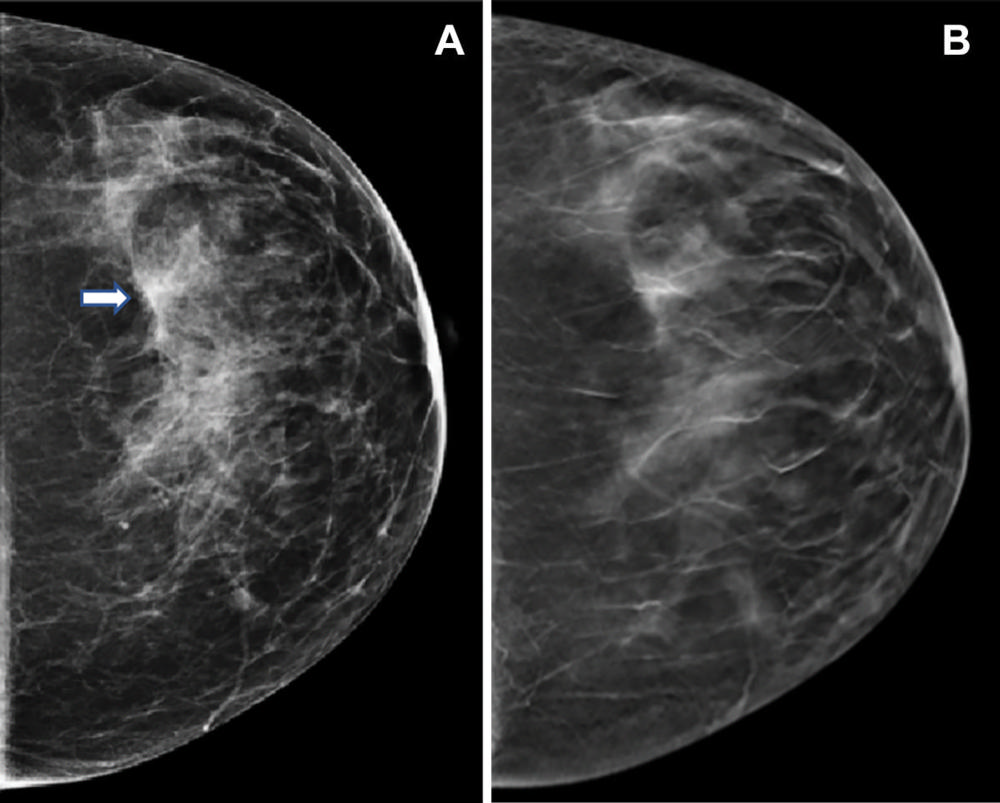

Figure 3. Images in a 47-year-old woman who presented for routine screening. (A) Craniocaudal digital mammogram shows scattered fibroglandular densities. On the left digital mammographic craniocaudal view laterally, an asymmetry (arrow) is present. (B) Left craniocaudal digital breast tomosynthesis image shows no suspicious lesion but rather a superimposition of normal fibroglandular and ligamentous structures.

High-res (TIF) version